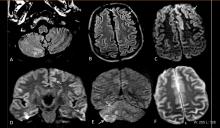

Pooja Rao, Ph.D., co-founder of Qure.AI and head of research and development for the company, explains how the company's artificial intelligence (AI)-based auto detection software can be used to analyze radiology images. The vendor offers a U.S. Food and Drug Administration (FDA)-cleared emergency room computed tomography (CT) scan automated AI analysis tool to immediately identify areas of suspected intracranial bleeds and cranial fractures. The software offers immediate feedback for suspected areas of interest for the attending physician or stat read radiologist. This can enable faster diagnosis and treatment in neuro imaging cases, especially in meeting door to TPA time in patients with ischemic stroke.

qER detects and prioritizes scans containing Intracranial bleeds, cranial fractures, mass effect and midline shift. Image markings, bleed subtypes and labels are not available in the United States.